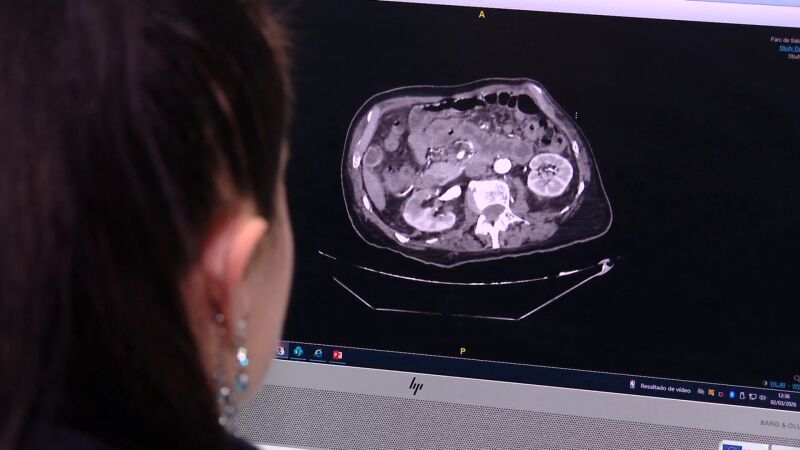

Según explica la doctora y cirujana del Hospital del Mar, Ana María González, se manifiesta con un fuerte dolor abdominal y la única forma de diagnosticar la enfermedad es a través de un TAC.

Hasta el momento, el protocolo marcaba que cuando un paciente llegaba a urgencias con dolor abdominal se le realizaba una exploración física y una analítica, que habitualmente no salía alterada y no levantaba sospechas. Horas más tarde, cuando el paciente empeoraba su situación era el momento en el que se procedía a realizar el TAC, prueba clave y única para confirmar o descartar el infarto intestinal. Pero, para la mayoría de los pacientes, ya era demasiado tarde y su situación era irreversible.

Ahora, con este nuevo protocolo se ha invertido el orden de las pruebas para conseguir un diagnóstico precoz. Es pionero en España y en el sur de Europa y se desarrolla, por el momento, únicamente en el hospital del Mar, en Barcelona. Ahora, cuando un paciente llega a urgencias y hay sospecha de que puede sufrir isquemia mesentérica aguda, se activa directamente este código y se le realiza la prueba TAC. Con ello se consigue un rápido diagnóstico que, en caso de confirmar la enfermedad, permite proporcionar un tratamiento precoz y reducir así la mortalidad.